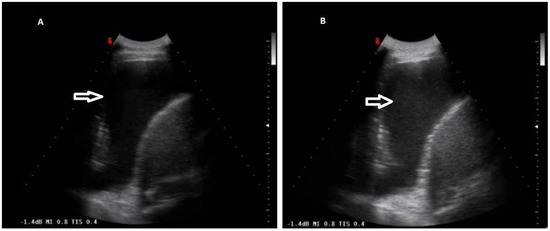

Figure 2. (A) TUS scan showing an anechoic effusion with consensual parenchymal atelectasis during thoracentesis with a multifrequency convex probe (3.5 MHz). The tip of the needle is highlighted by a white arrow. (B) The corresponding CT scan shows a smooth thickening of the peribronchovascular interstitium and a bilateral pleural effusion with passive atelectasis of lower lobe in the right lung (black arrow).

According to the macroscopic appearance, in 54 patients (14.96%) pleural effusion was hemorrhagic, in 297 (82.27%) citrine, and in 10 patients (2.77%) torbid. Based on the composition of the drained fluid, pleural effusions were classified as transudate in 27 patients (7.48%) and exudates in 334 patients (92.52%). On TUS examination, pleural effusions showed an anechoic appearance in 165 patients (45.71%), a heterogeneous ipo-iperechoic appearance (i.e., complex nonseptated) in 174 patients (48.20%), and a homogeneous hyperechoic appearance in 22 patients (6.09%). All the pleural effusion (100.0%) classified as transudates according to Light’s criteria showed an anechoic TUS appearance (Figure 2).

Only the exudative effusions showed a complex nonseptated or a hyperechoic TUS appearance. Considering the pleural effusions classified as exudates, the frequency distribution of the anechoic TUS appearance (n = 138/334, 41.32%) and of the complex nonseptated pattern (n = 174/334, 52.09%) were statistically higher than that of the homogeneous hyperechoic one (22/334, 6.59%), with a p-value < 0.0001. The number of complex nonseptated exudates was statistically higher compared to that of the anechoic ones (p = 0.005) (Figure 3).